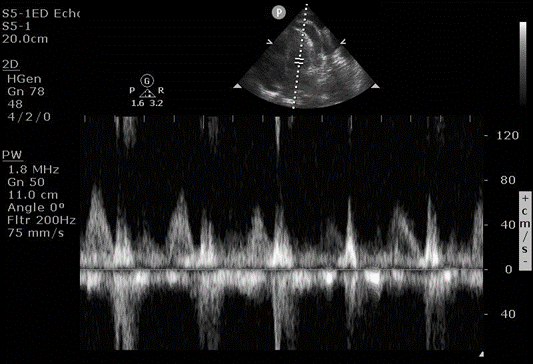

An apical four chamber view was obtained, and a pulsed wave Doppler was placed in the left ventricle, and an E and A wave were generated over the patient’s respiratory cycle. (Figure 2) This showed a > 30% variation in the E wave, suggesting sonographic pulsus paradoxus.

Figure 2. Mitral valve inflow velocity with pulse wave Doppler, showing variation in the E wave (first peak) over a respiratory cycle

Looking at respiratory variation in blood flow through the mitral valve is often thought of as difficult to acquire but can be performed reliably after practice. A good apical four chamber view is a necessity, and the pulsed wave Doppler gate is placed within the left ventricle at the coaptation of the mitral valve leaflets, generating an E wave first (early diastole) and an A wave second (atrial kick). The ED physician should ask the patient to take a breath, and an E and A wave are generated throughout the respiratory cycle. The image is frozen, and the amplitude of the largest and smallest E wave is measured. Figure 2 If the difference is greater than 30%, this finding is very specific for cardiac tamponade. While this same approach can be performed using the tricuspid valve, the right ventricle can be more difficult to obtain a clear view of, and the difference in E wave amplitude must be greater than 60% to be considered positive. While other sources say the mitral valve needs greater that 25% variation, and the tricuspid valve needs greater than 40% variation for tamponade, using 30% and 60% respectively will increase specificity.